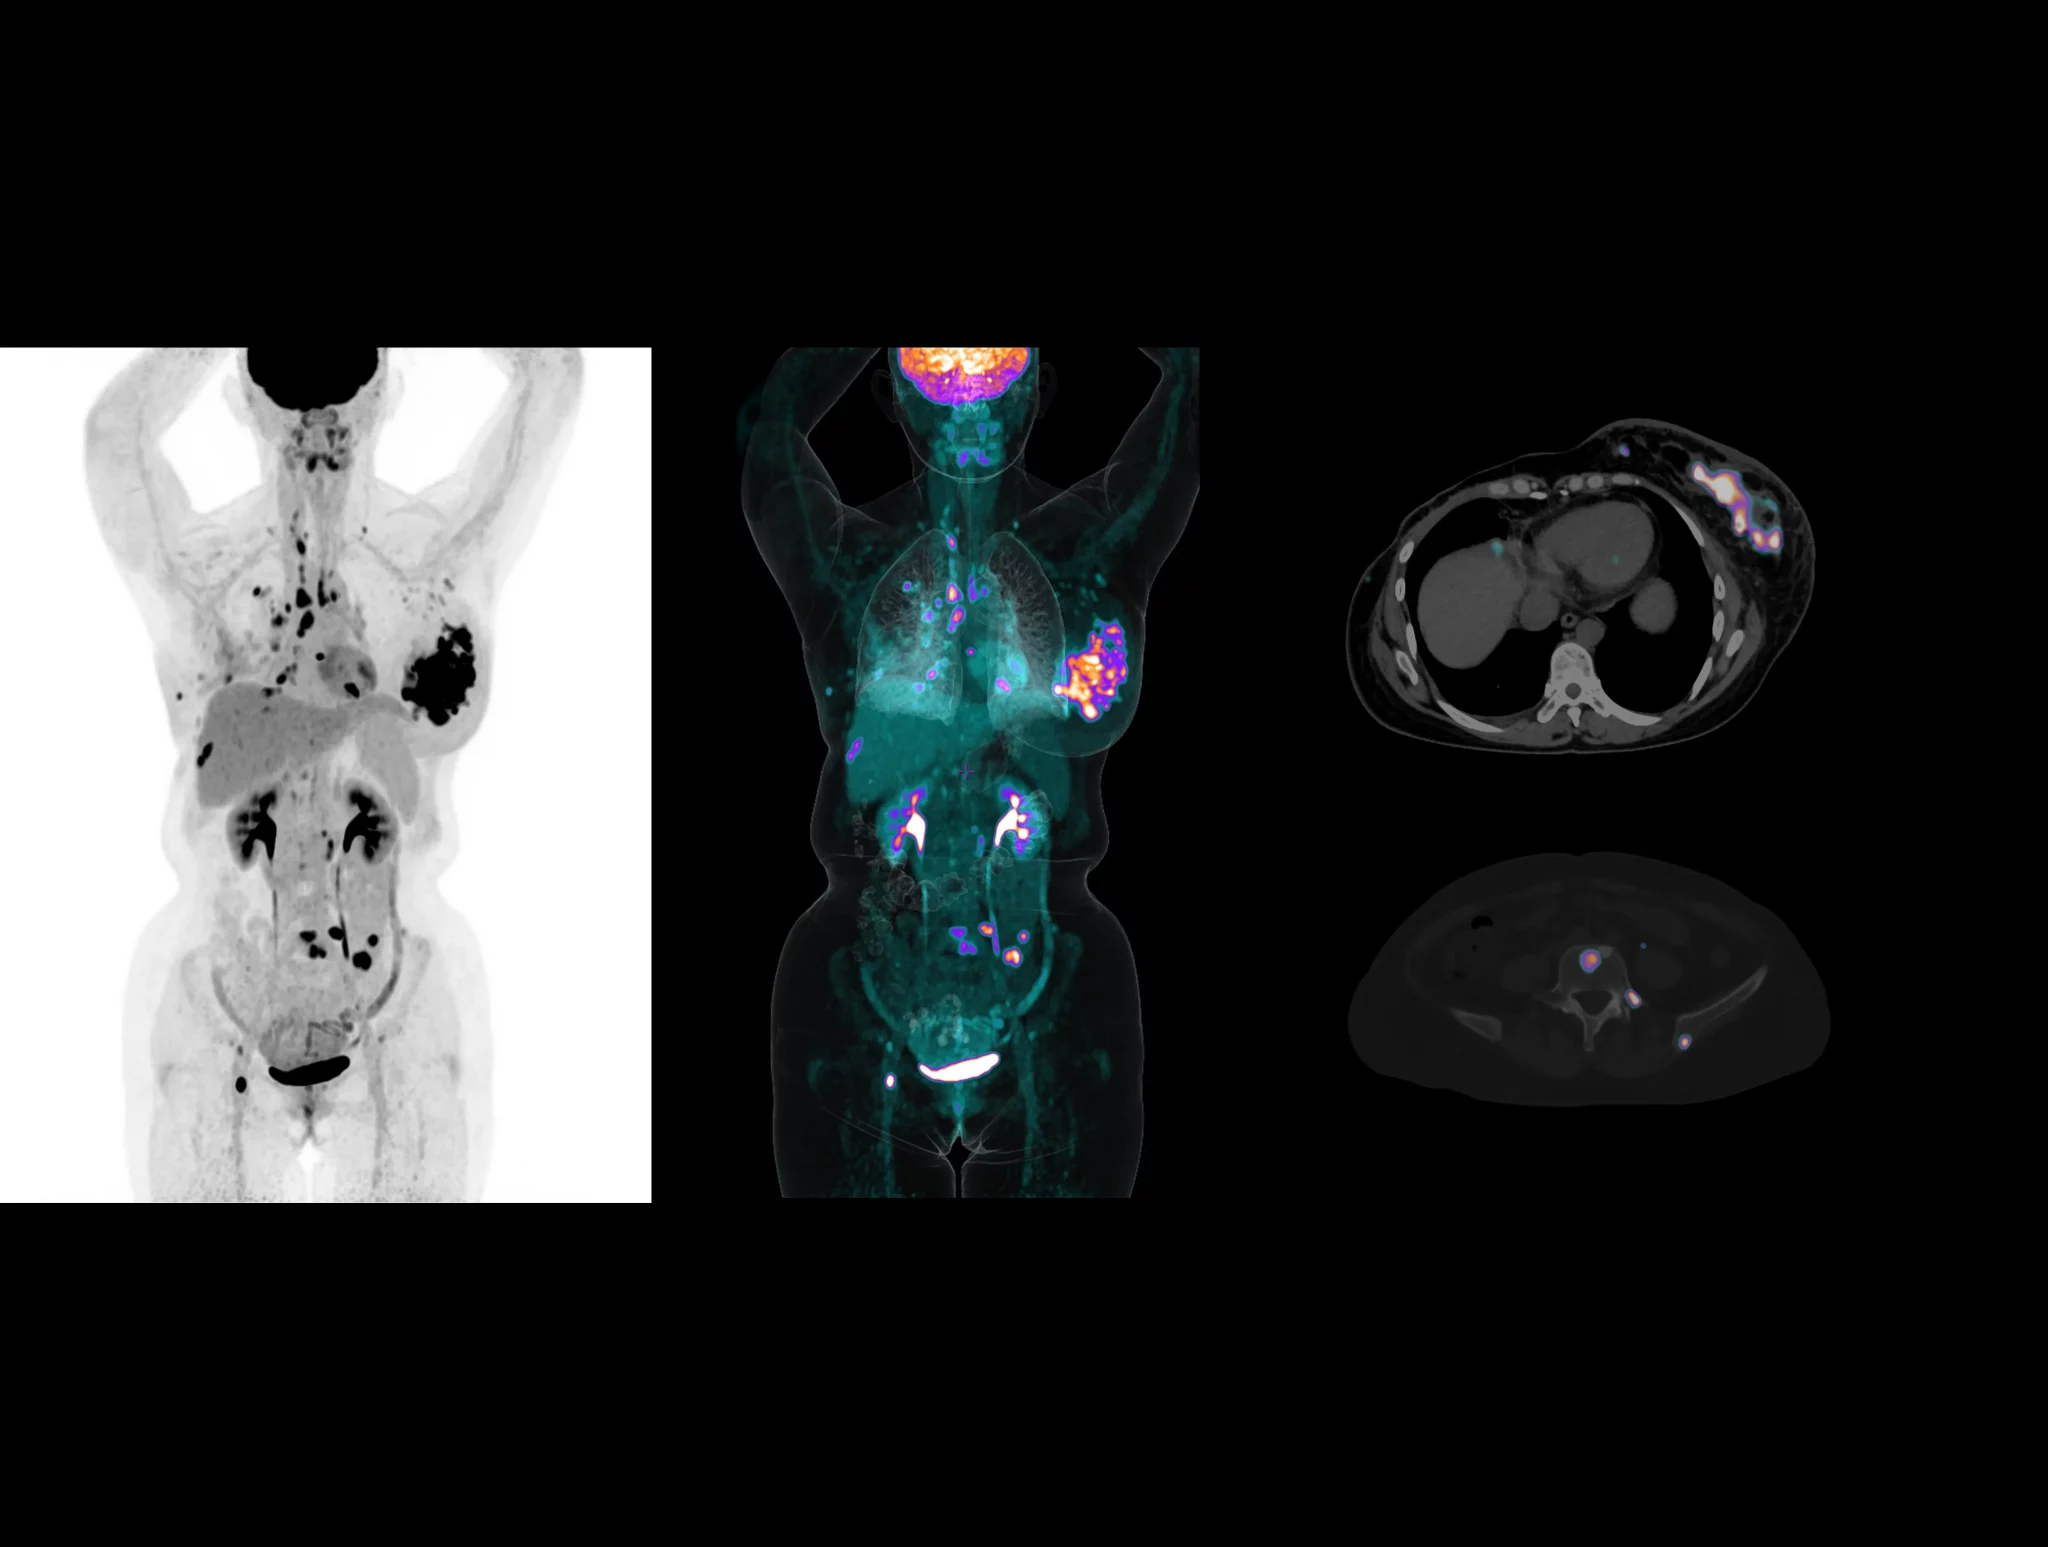

With the ultra-high system performance, uMI Panorama faces up to the challenges of tracers with different half lives and the complex scanning conditions, without compromise for image quality.

Click on different tracers to see the images.

Case Gallery